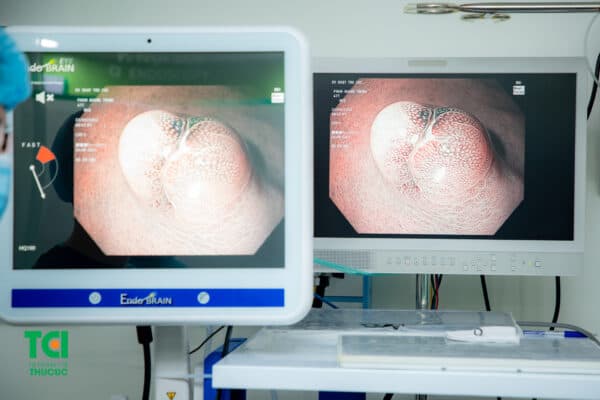

Cận hình ảnh polyp dạ dày được phát hiện khi người bệnh thực hiện nội soi đường tiêu hóa trên.

Ekip nội soi đang thực hiện cắt polyp ngay trong quá trình thực hiện thủ thuật.